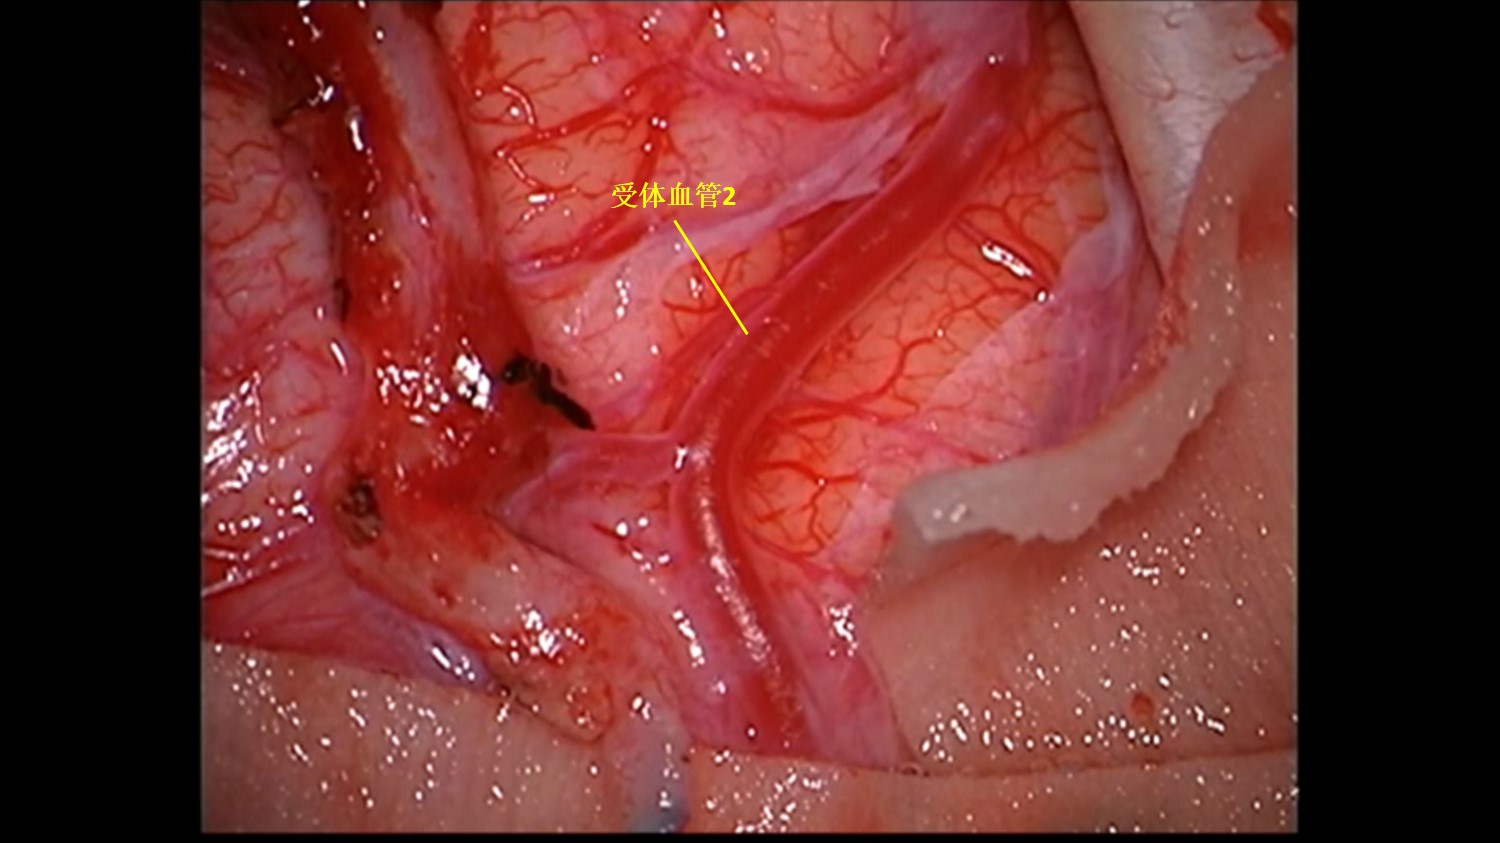

受体血管2:血流量较好,管壁薄。

吻合口2